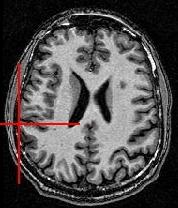

You can for instance visualize simultaneously the bias corrected image and the brain mask, relying on Anatomist linked cursor:

Another way consists of the two volume fusion. brainVISA's eye can do it for you. If you prefer manual work, select the two volumes, give a unicolor colormap with the ufusion extension to the mask, and choose the linear combination fusion mode: